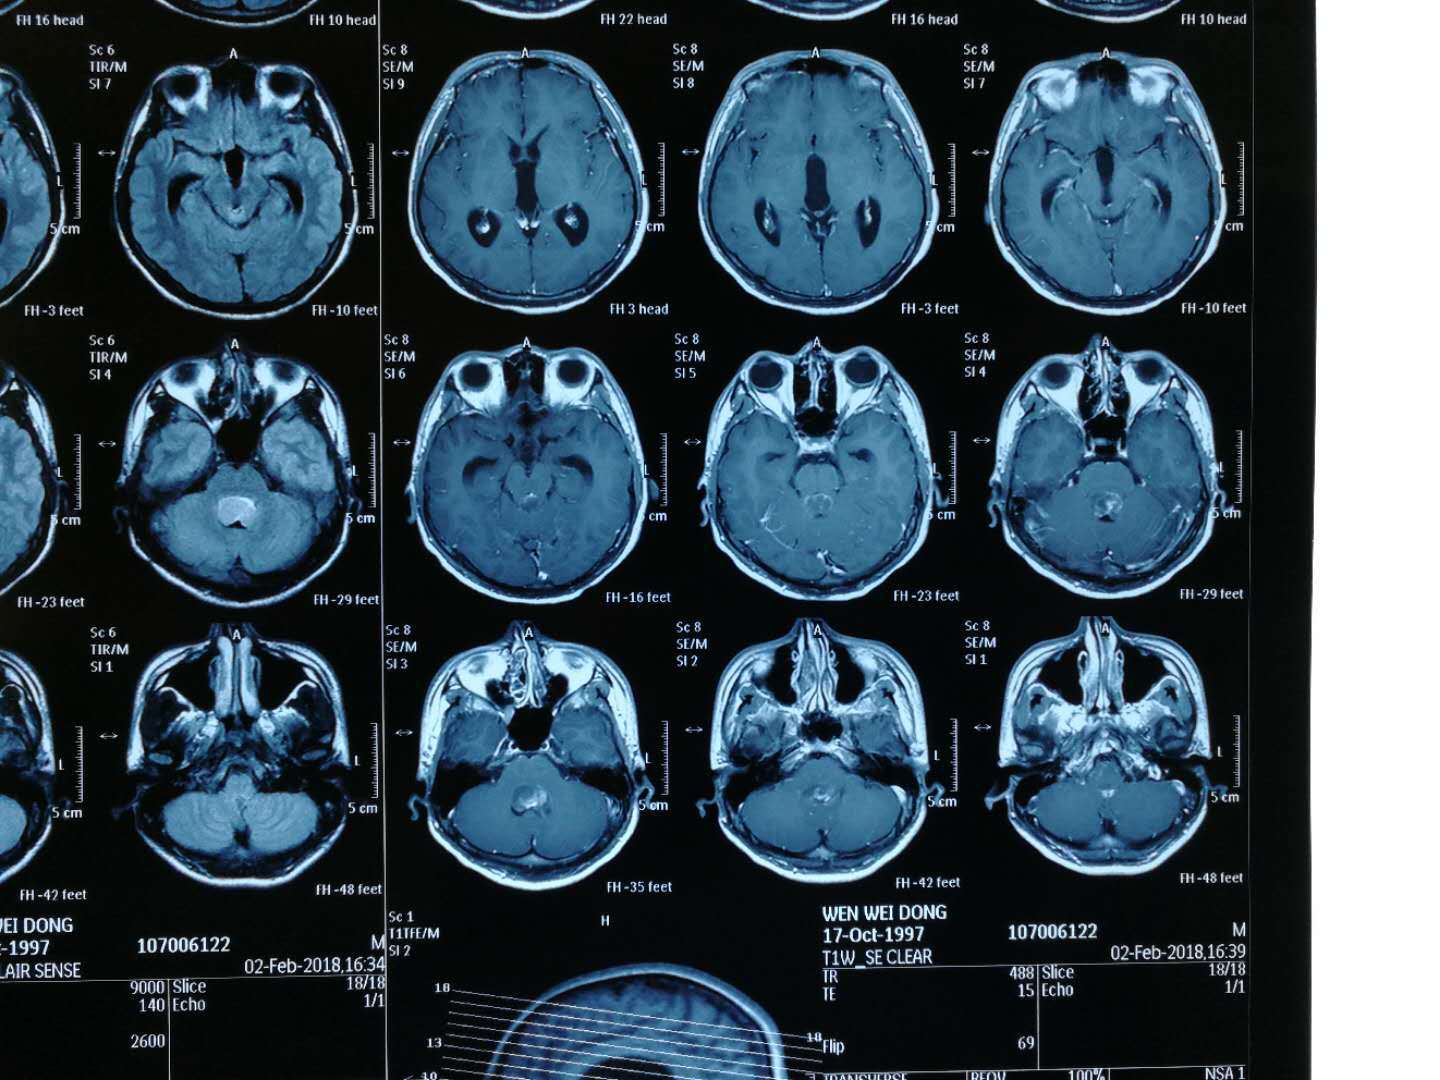

头颅核磁共振(mri)检查:四脑室肿瘤,不均匀增强,上达中脑导水管下口

其它 经颅多普勒(tcd)术中脑血流监测一例 写美篇

头颅mr横断面解剖中英文对照版,音乐 影像 解剖原来是另一番新天地